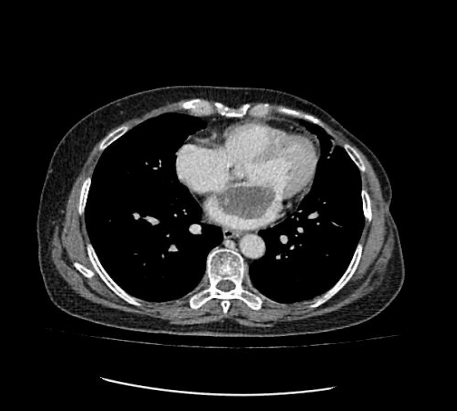

患者為一名57歲的女性,心慌、胸悶的癥狀已有一年多,一直以為是“感冒”而沒放在心上。最近經(jīng)人介紹到我院檢查,經(jīng)心臟超聲檢查發(fā)現(xiàn)左心房上長了一個(gè)雞蛋大小的黏液瘤。雖說是良性的,但生長位置在二尖瓣口,如果黏液瘤碎片或瘤體表面血栓脫落,可發(fā)生體循環(huán)或肺循環(huán)的栓塞,隨時(shí)有猝死的危險(xiǎn)。以往此類疾病必須通過傳統(tǒng)胸部正中切口實(shí)施手術(shù),病人術(shù)后要經(jīng)過3-6個(gè)月左右的恢復(fù)期,患者創(chuàng)傷大、恢復(fù)慢、出血較多、切口瘢痕明顯、心理負(fù)擔(dān)重,無論是對身體還是心理都是一次嚴(yán)重創(chuàng)傷。為患者實(shí)施全胸腔鏡技術(shù)摘除左心房黏液瘤手術(shù),在不破壞患者破壞胸骨穩(wěn)定性的前提下,只需在患者胸壁上開2個(gè)“鑰匙孔”樣大小觀察孔和1個(gè)4cm的操作孔即可進(jìn)行手術(shù),最大限度減少術(shù)后疼痛和創(chuàng)傷,縮短術(shù)后恢復(fù)時(shí)間。